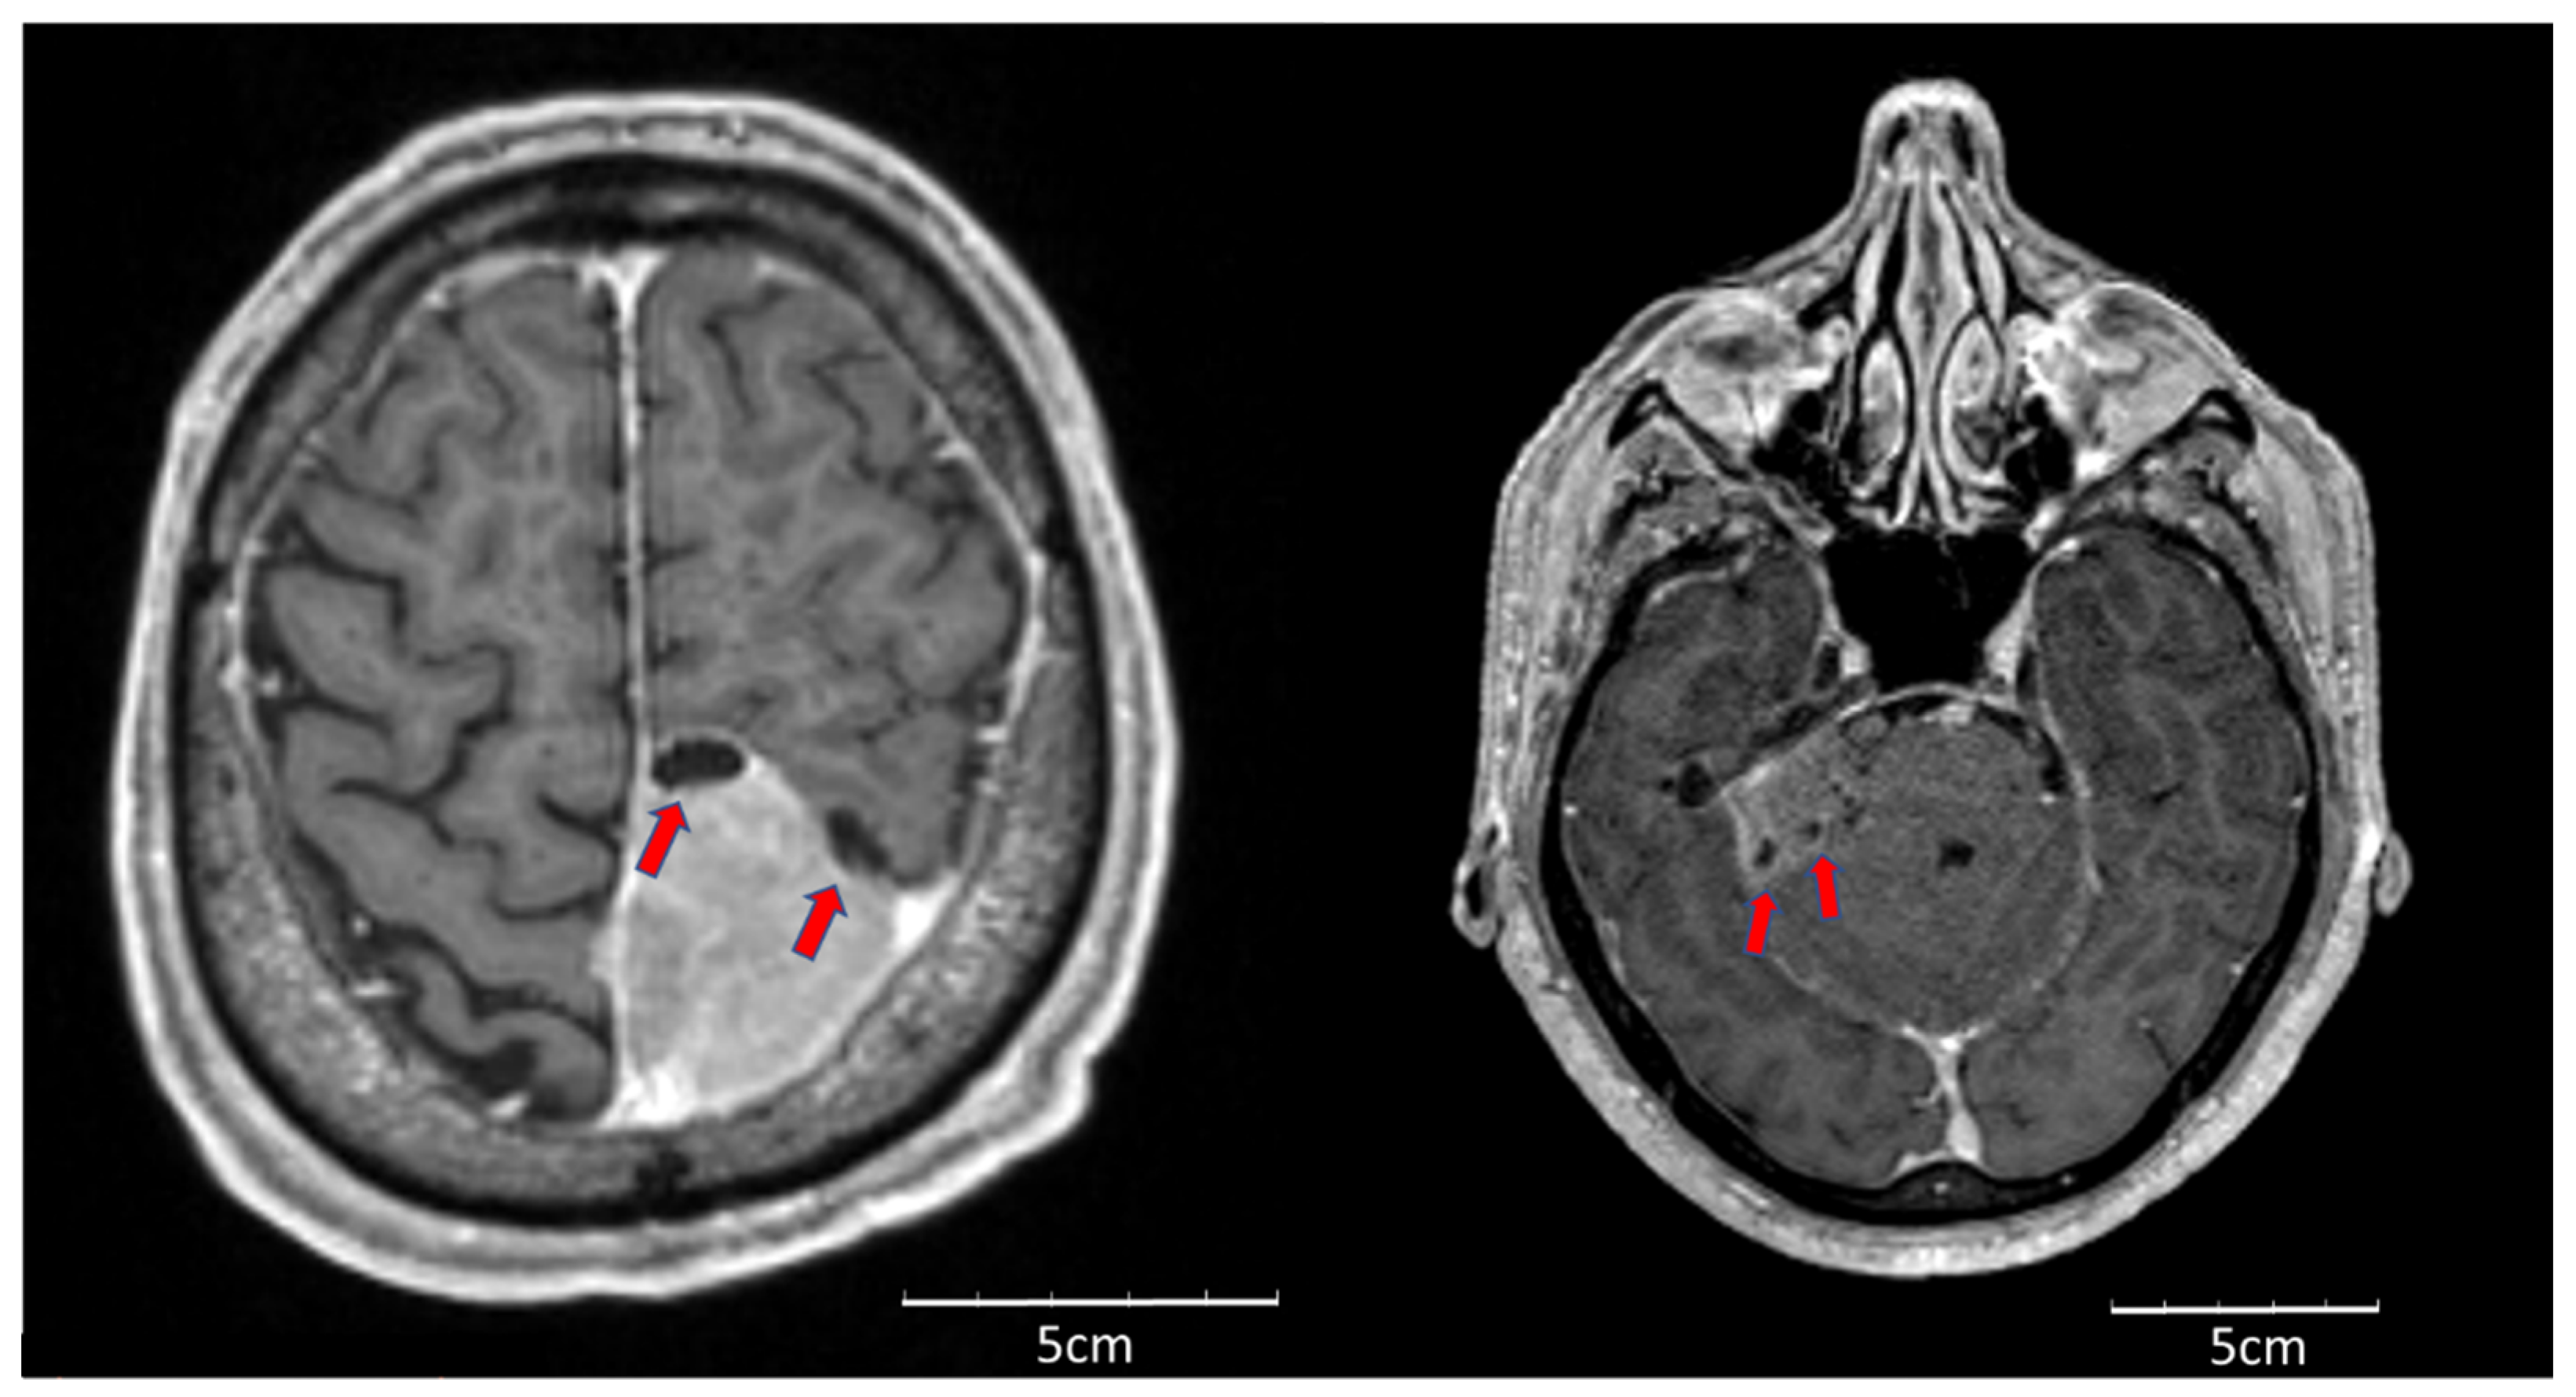

| Cystic component† | 21.74 | 3.79–124.54 |

| Cystic component † | 20.21 | 2.46–166.02 |